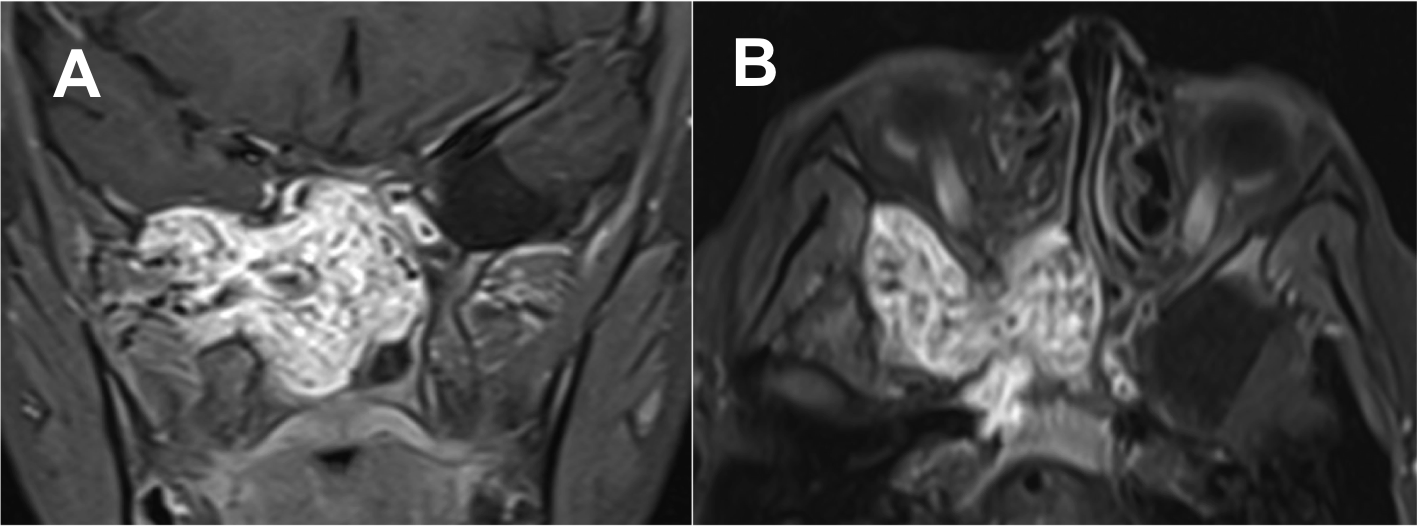

Introducción: La cirugía endoscópica endonasal se ha convertido en una herramienta fundamental para el manejo de patologías que comprometen la base de cráneo. En casos bien seleccionados, estas técnicas permiten resecciones quirúrgicas con una menor morbilidad sin comprometer los principios oncológicos de resección. Con el desarrollo de instrumental especializado, nuevas tecnologías y la experiencia de los cirujanos, la cirugía endoscópica endonasal se usa cada vez más en cirugía de base de cráneo en niños.

Diseño: Estudio observacional descriptivo de tipo serie de casos. Metodología: se describe la experiencia con pacientes pediátricos llevados a cirugía endoscópica endonasal para manejo de tumores de base de cráneo en el Instituto Nacional de Cancerología entre julio de 2014 y diciembre de 2016.

Resultados: Fueron intervenidos 8 pacientes entre los 2 y 14 años, con una edad promedio de nueve años y un seguimiento promedio de 16 meses. En el 75% se hizo una resección total del tumor. Un paciente requirió una reintervención y un paciente fue sometido a radiocirugía post-operatoria. 1 paciente falleció a pesar de múltiples intervenciones, quimioterapia y radioterapia.

Conclusión: La cirugía endoscópica endonasal para tumores de base de cráneo puede ser utilizada de forma segura en los pacientes pediátricos, es una técnica que en casos bien seleccionados pueden ofrecer excelentes resultados disminuyendo la morbilidad y complicaciones de las técnicas abiertas.